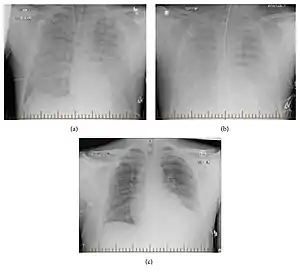

| Progression of hantavirus pulmonary syndrome | |